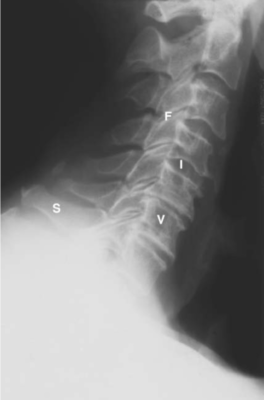

LIÊN HỆ HÌNH ẢNH HỌC

Cột sống cổ

Các chữ viết tắt:

- V = Vertebral body; thân đốt sống

- D = Intervertebral disc; đĩa gian sống

- Sc = Spinal cord; tuỷ sống

- S = Spinous process; mỏm gai

- N = Neural foramen; lỗ thần kinh

- P = Pedicle of vertebral arch; cuống cung

- I = Intervertebral disc space; khoảng đĩa đệm

- F = Facet joints; khớp diện nhỏ/facet

- T = T1 transverse process; mỏm ngang T1

Cột sống thắt lưng